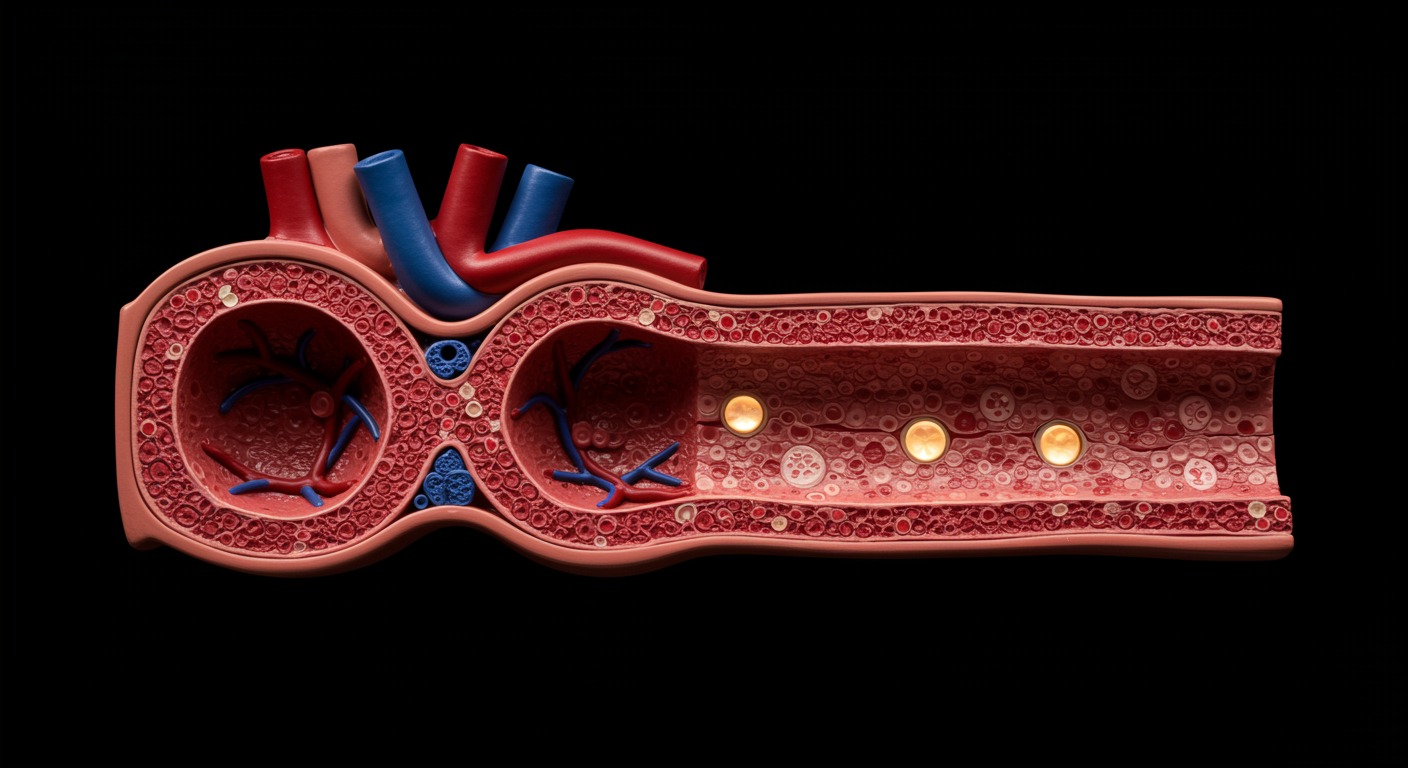

The endocrine system orchestrates a delicate balance of hormones that regulate nearly every function in the human body. From metabolism and growth to mood and reproduction, hormones serve as chemical messengers that coordinate complex physiological processes.